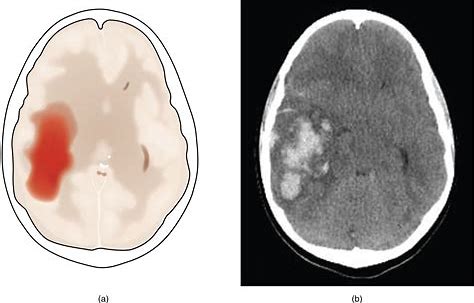

随着我国社会的进步和生活习惯的改变,高血压的发病率呈现出年轻化的趋势,而且高血压所引起的并发症也在逐年增加。40岁左右的患者因高血压导致脑出血的病例,在临床上已经不再罕见。这都是因为高血压患者对血压的管理不善导致的,其中很大一部分是由于不良的生活习惯引起的。

这部分患者在第2天会出现血压反跳性升高,这种升高往往是非常剧烈的,血压波动非常大容易诱发脑出血,从而危及患者生命。在张医生治疗的40多岁的患者中,大多数在发病前都有大量饮酒的病史。